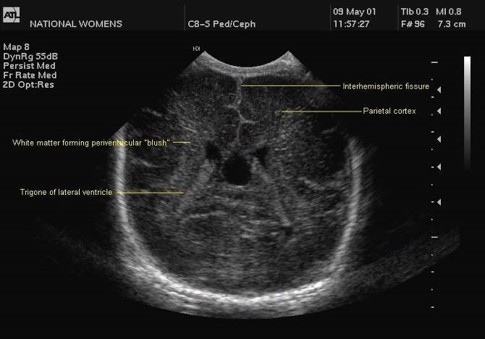

Measurement of the ventricular system needs to be performed on a symmetrical, easily reproducible view. The ventriculo-cranial ratio (VCR) is the ratio of distance between the lateral sides of the ventricles and the biparietal diameter. This is usually expressed as a percentage with a normal value of around 33-36% in a preterm infant. This value is of most use in monitoring the degree of change between successive measurements. An increasing VCR should trigger frequent reassessments with measurements of the cerebral resistive index (see below).